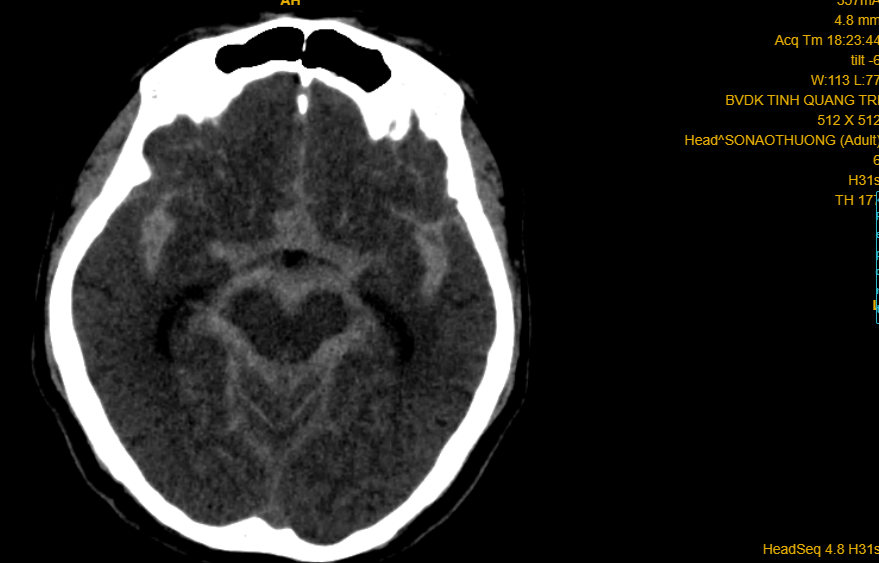

Phim CT-scan trường hợp số 02 (cháu gái 10 tuổi) xuất huyết não